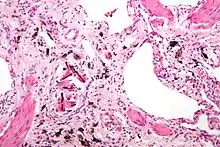

Micrograph of asbestosis (with ferruginous bodies), a type of pneumoconiosis. H&E stain.